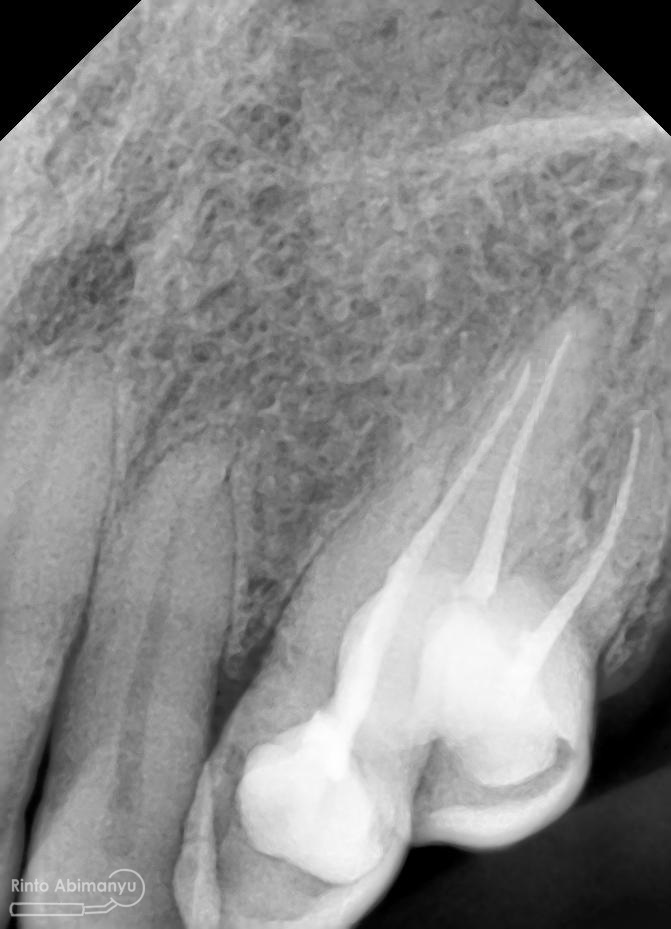

Setelah melihat hasil ronsen trial guttap maka pengisian siap dilakukan… Untuk pengisian saluran akar saya memakai tehnik warm vertival condensation memakai alat Element Obturation Unit (SybronEndo) dan siler AH plus (Dentsply)…

Setalah pengisian usahakan kamar pulpa dibersihkan dari sisa2 siler dan kotoran2 agar bahan adhesive yang kita pakai untuk restorasi dapat melekat maksimal.. Untuk basis saya menggunakan X-tra Base (Voco) kemudian diatasnya memakai komposit Z 350 XT (3M)…

Setelah itu dilakukan pengambilan ronsen kembali…

Alhamdulillah perawatan ini tidak ada kendala dan bisa diselesaikan dalam satu kali kunjungan langsung dua gigi… Ronsen sangat penting dalam prosedur perawatan saluran akar, jadi pesan saya adalah “No Xray, No Endo” 🙂